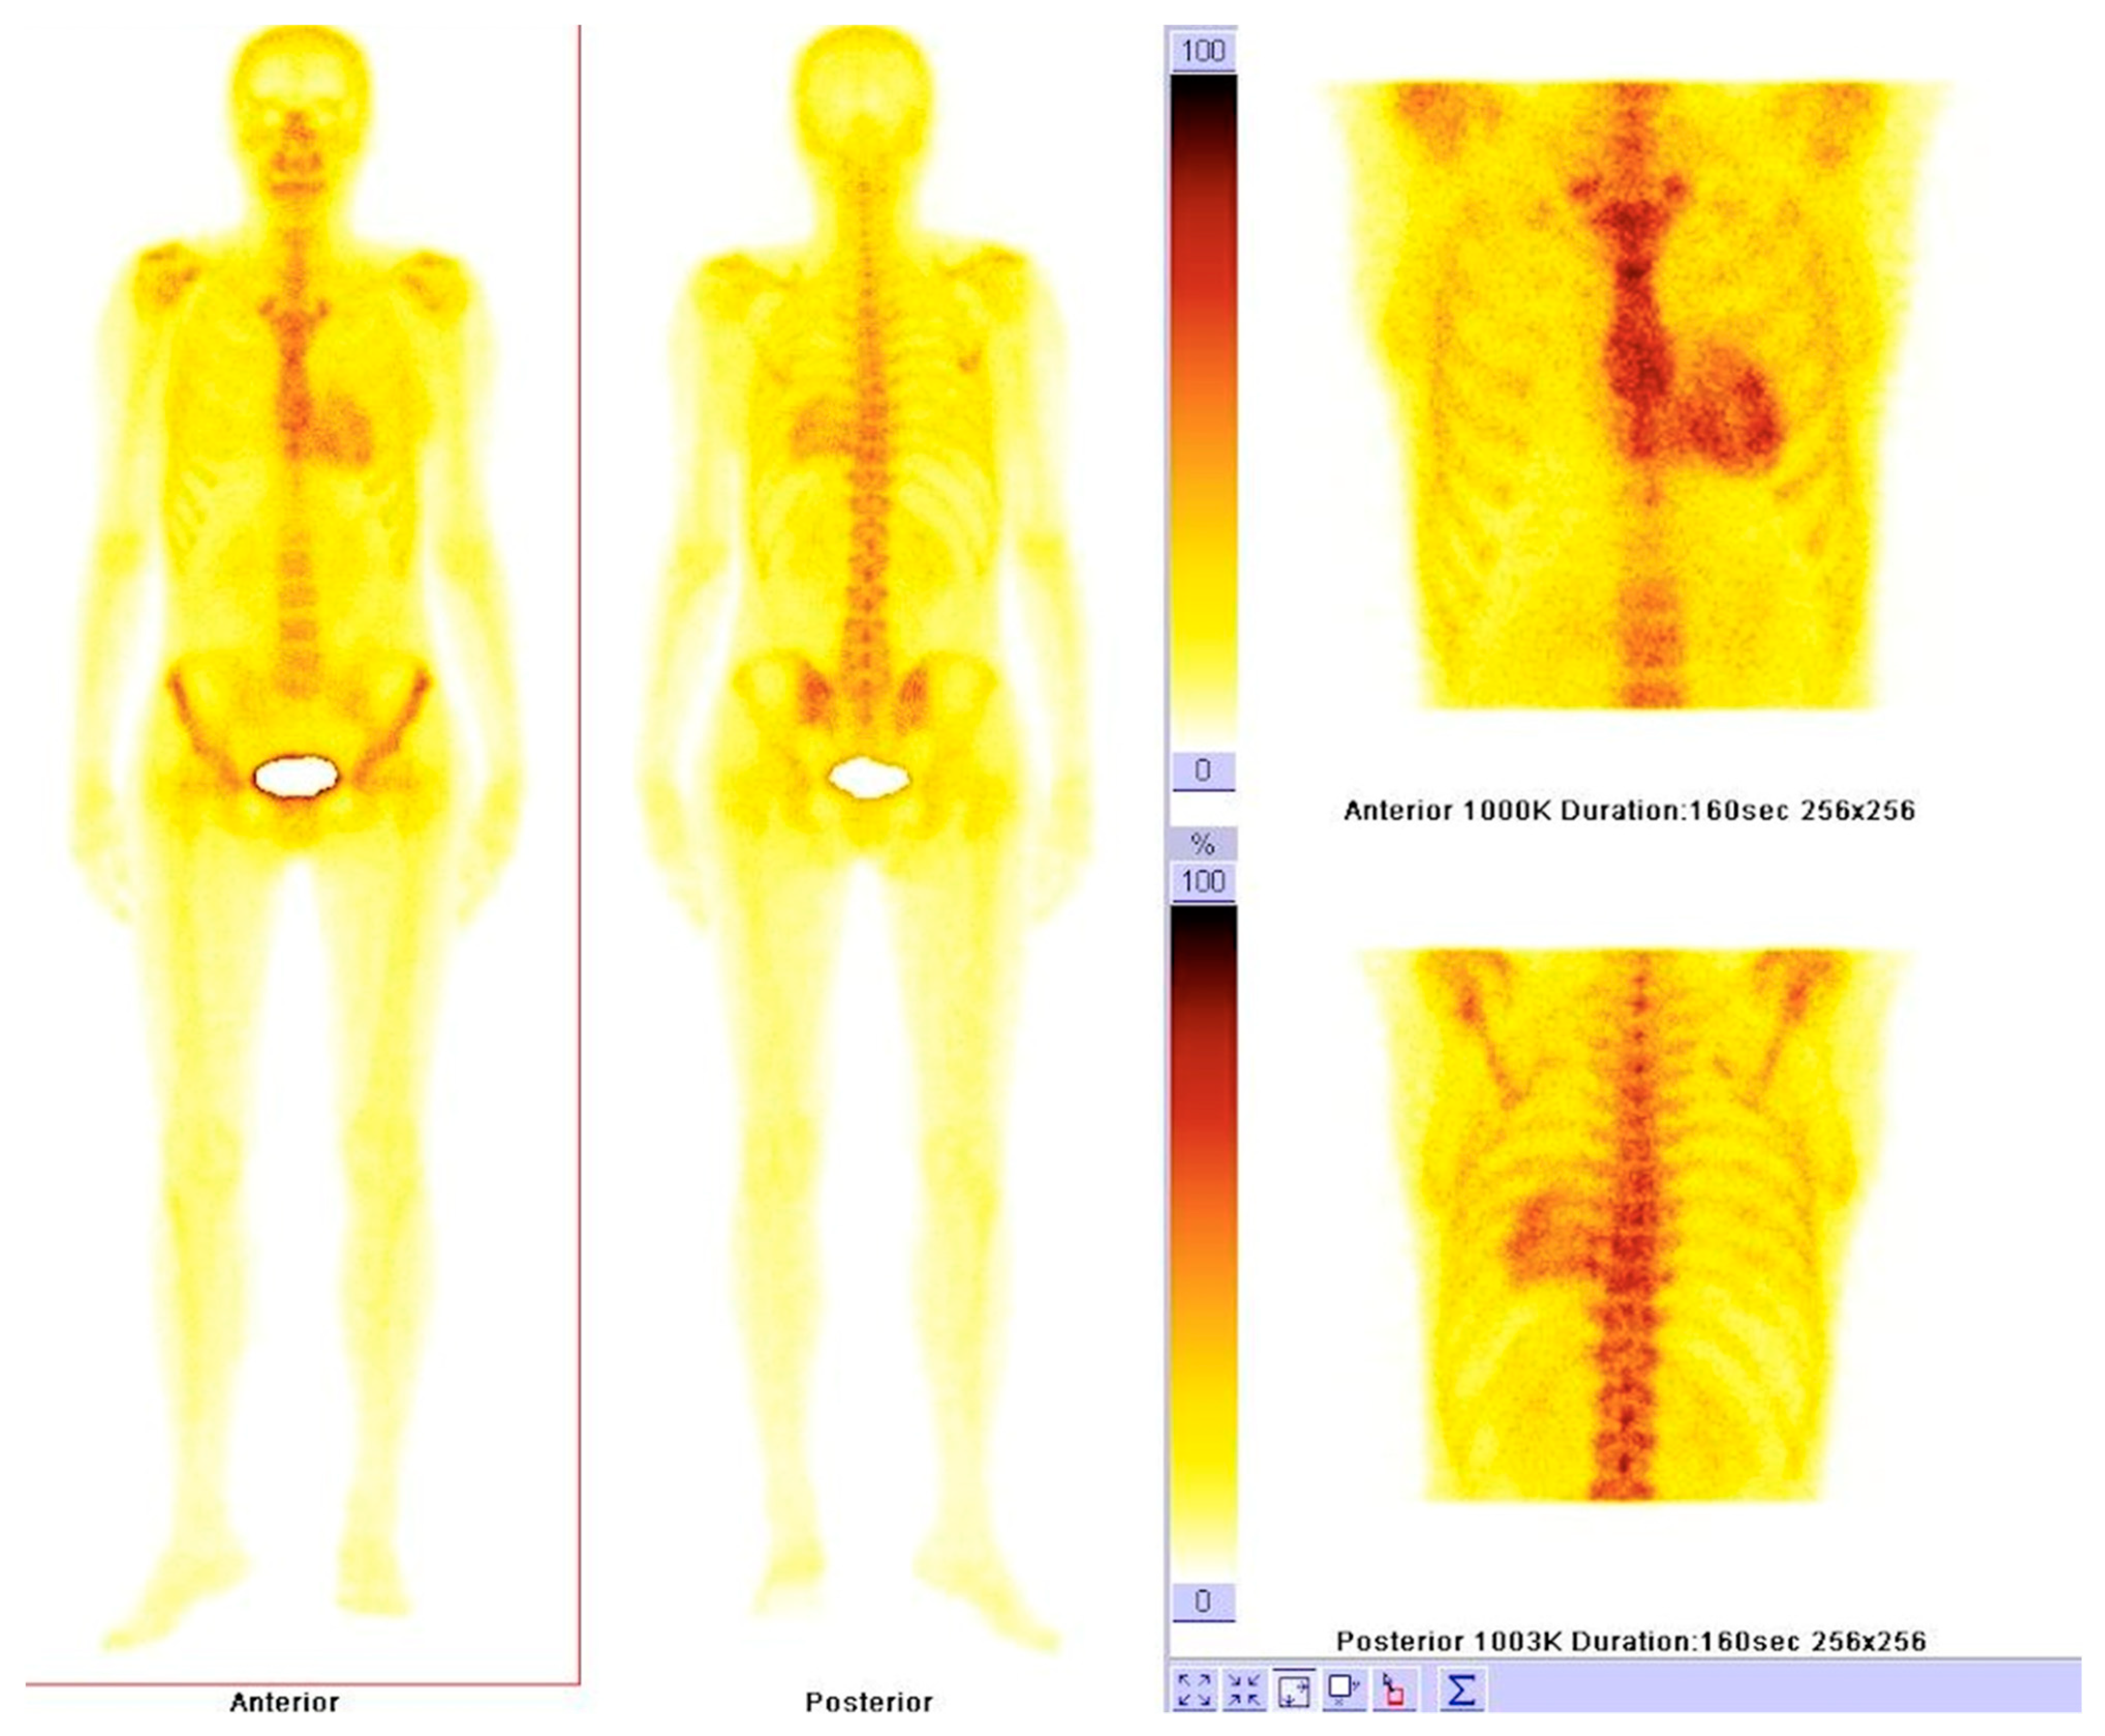

6.1. Nuclear Imaging in Amyloidosis

6.2. Nuclear Imaging in Sarcoidosis

6.3. Nuclear Imaging in Hemochromatosis